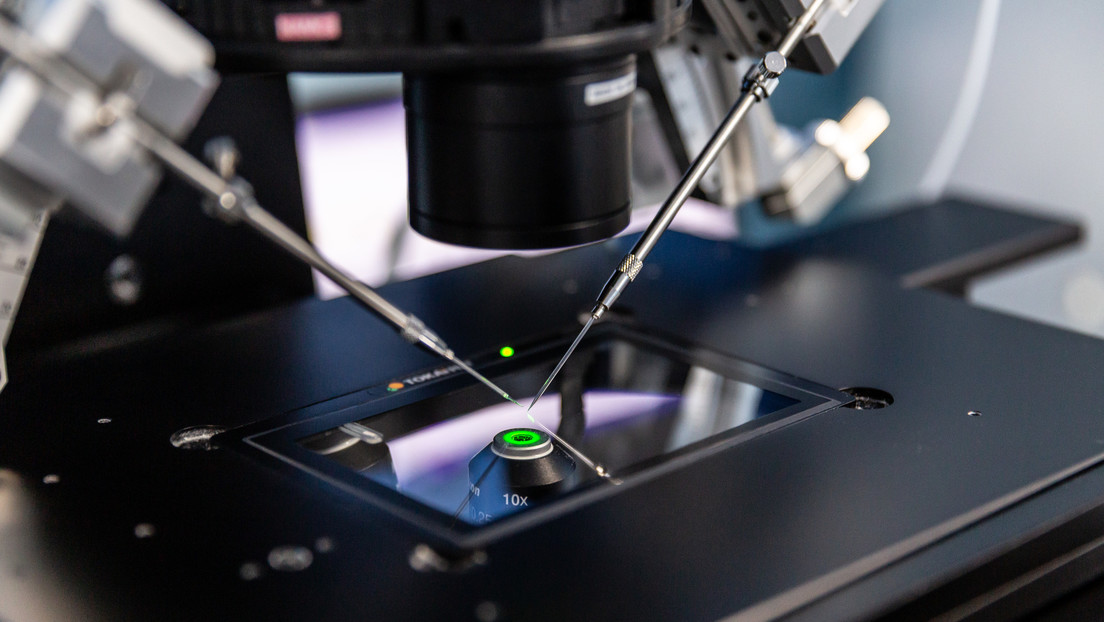

Nacen los primeros bebés concebidos con ayuda de un robot inyector de semen

Han nacido los primeros dos bebés concebidos con ayuda de un robot capaz de inyectar esperma en óvulos durante el proceso de fecundación in vitro (FIV), informó esta semana el portal MIT Technology Review. El...